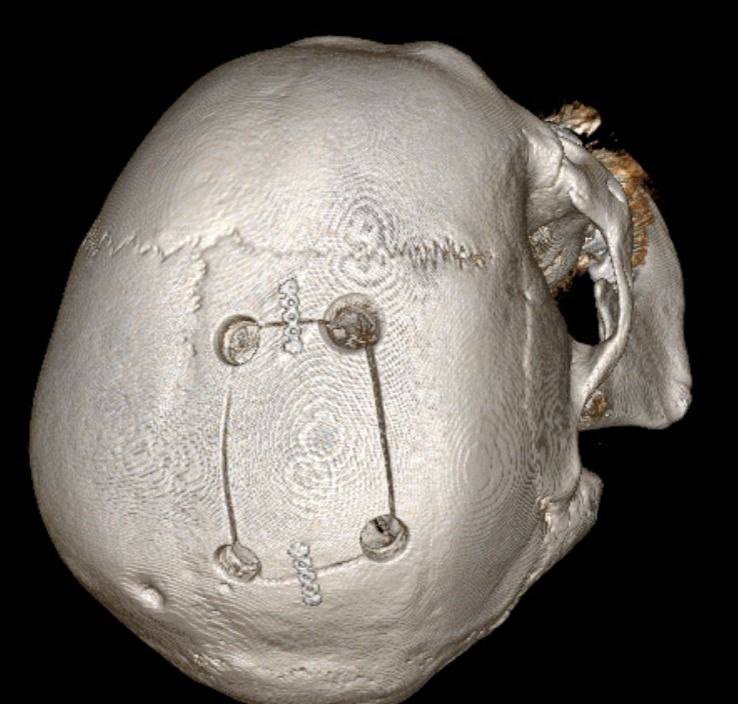

Нейрохирурги выполнили костно-пластическую трепанацию черепа и полностью удалили опухоль.